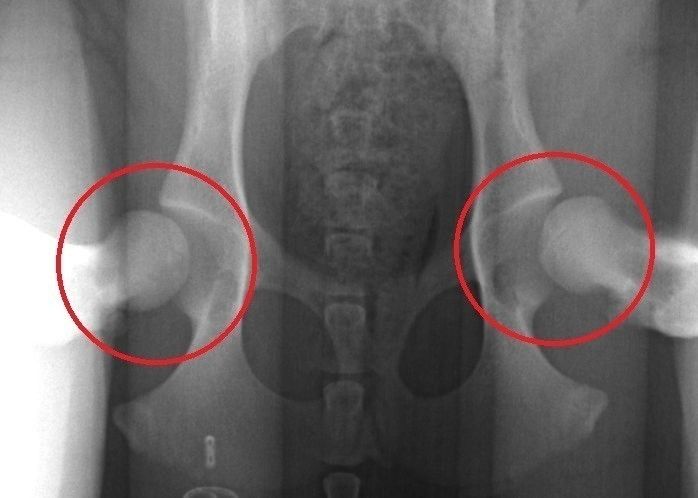

「うちのコ、お尻をフリフリして歩くのがクセなの♪」などと、のんきなことは言っていられません。もしかしたらそれは「股関節形成不全」という関節まわりの病気が原因かも。後ろ足を引きずる、立ち上がるのが遅いなどの症状が出ることもあります。

病気が進行すると歩けなくなることもあるので、なりやすいといわれている大型犬はとくに、子犬のときから検診を受けて異常がないかチェックするよう心がけましょう。

早期発見のためのエックス線検査で発見された股関節形成不全の例。円内の股関節にゆるみが見られます(症例写真提供/南 直秀先生)